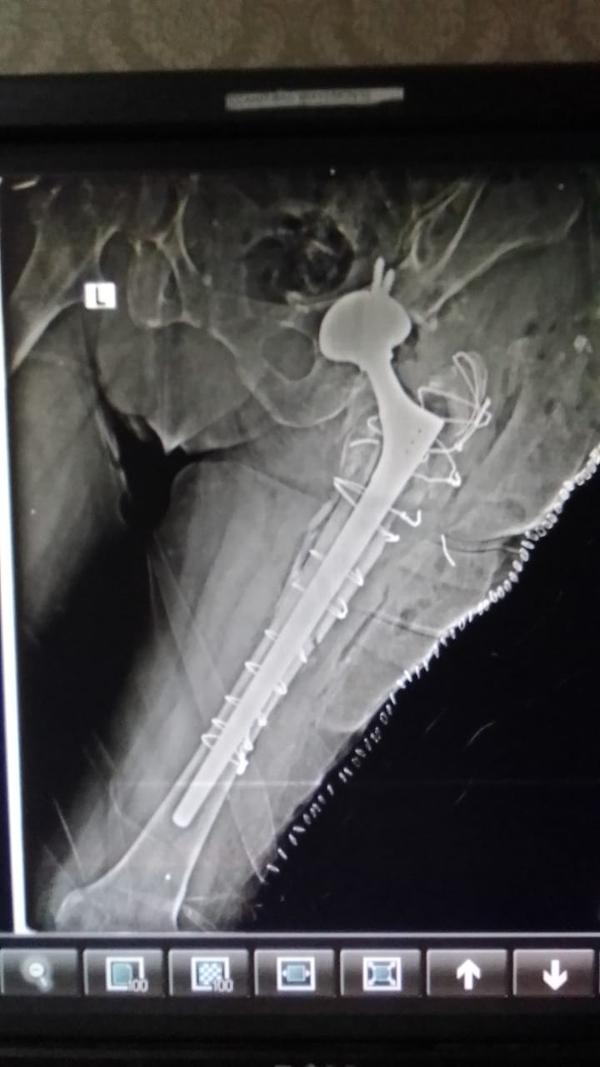

Revision Hip And Knee Replacement

Dr Randive has 25 years experience in Revision Knee and Revison Hip Replacement surgeries. It took him more than 25 years of training hard work and thousands of surgeries to achieve excellence in Revision Knee and Hip Surgeries. He has successfully achieved this milestone through extensive training.